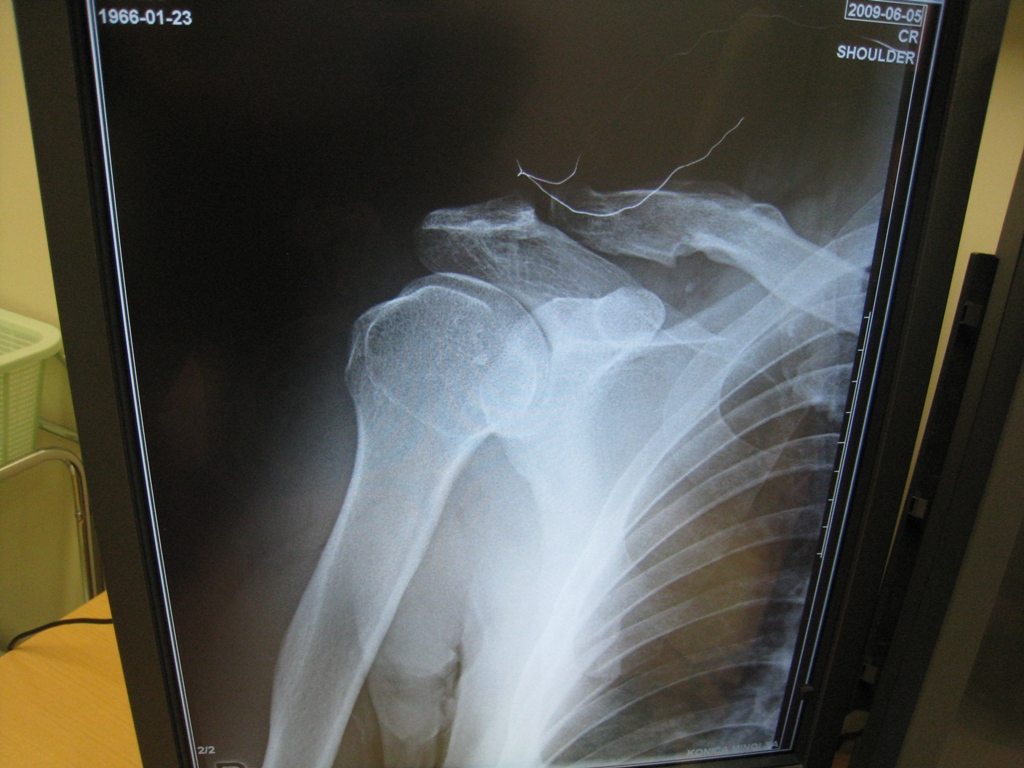

トレーニング中にヒョンなアクシデントから右肩を外傷性肩関節脱臼・靭帯損傷・・

お陰で短い時間で直ぐ検査をして、元通りにはめてもらったが、はめ込んでる時の更なる激痛は酷かった! それもはめ込むまで1時間以上もかかってやっとのことだったから始末が悪い。

損傷した肩は脱臼がクセや今後手術にならないように数週間は右腕固定・・・なんだって。

関節唇という軟骨を損傷しているため、しっかり固定しても再脱臼の危険性は高くなるらしく、関節唇ってのは二度と再生もしない。

(写真左が脱臼しているレントゲン画像で、写真右が元に戻した後の画像)